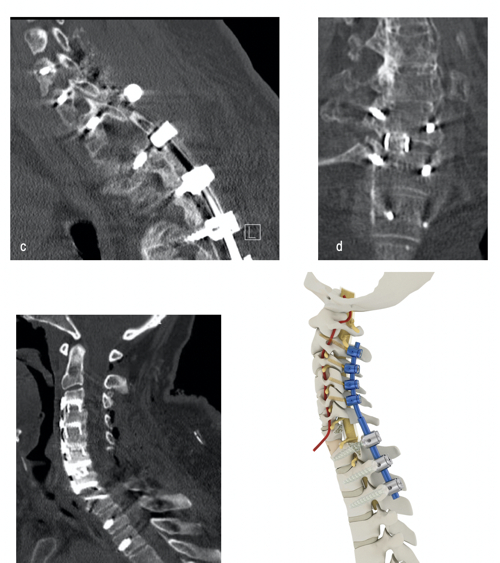

The spinal research team focuses on three fields of interest: improving clinical and functional patient outcome, experimental regenerative attempts, and biomechanical investigations into spinal pathologies (Fig. 2). We have also conducted experimental studies to elucidate the benefits of therapeutic approaches for intervertebral disc diseases with a self-complementary adeno-associated virus-mediated knockdown of specific gene loci (ADAMTS4). Our experimental laboratory focuses on regenerative attempts to improve therapeutic strategies.

Minimal invasive surgery using state-of-the-art neuronavigation systems and imaging technology is another clinical research interest. As well as taking part in a prospective multicentre study (EUROSPIN) to evaluate the accuracy of pedicle screw placement using a “free-hand”, a navigated or robot-guided technique, we are involved in an international, multicentre machine learning (ML) algorithm for outcome prediction after lumbar spinal fusion, with the aim of development and external validation of a robust prediction tool.

Additionally, the treatment options of complex spine instrumentations in the case of cervical deformities, neoplastic infiltrations or infectious diseases are being investigated biomechanically, in collaboration with the biomechanical laboratory of the Department of Orthopaedics and Traumatology.

- Surgical nuances and construct pattern influence construct stiffness in C1-2 stabilisations: A biomechanical study of C1-2 gapping and advanced C1-2 fixation.

- Biomechanical investigation of lumbar hybrid stabilisation in two-level posterior instrumentation.

- Hartmann S, Thomé C, Abramovic A, Lener S, Schmoelz W, Koller J, Koller H.: The Effect of Rod Pattern, Outrigger, and Multiple Screw-Rod Constructs for Surgical Stabilization of the 3-Column Destabilized Cervical Spine – A Biomechanical Analysis and Introduction of a Novel Technique. Neurospine. 2020 Sep;17(3):610-629. doi: 10.14245/ns.2040436.218. Epub 2020 Sep 30.